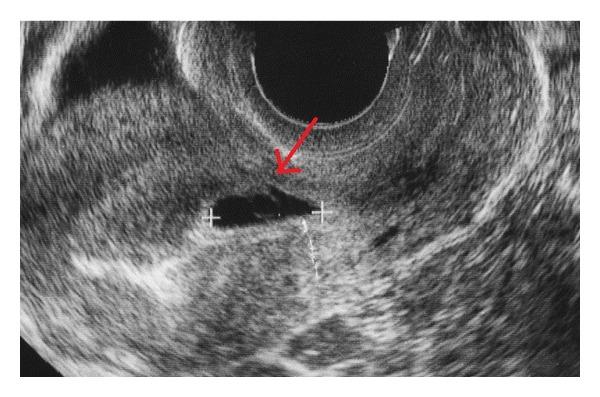

We report our experience with a case of presumptive cesarean scar pregnancy, based on detection of a gestational sac (GS) in early pregnancy at the site of a previous cesarean scar. The GS grew into the uterine cavity as the pregnancy progressed, showing an ultrasound image similar to that of a normal pregnancy. Thus, the pregnancy continued, resulting in a viable birth at 28 weeks of gestation. Cesarean scar pregnancy is classified as myometrial implantation or implantation growth into the uterine cavity. In the latter type, the gestational sac moves upward with increasing gestational weeks and it shows the same ultrasound image as a normal pregnancy. Therefore, the diagnosis must be made in the early pregnancy.